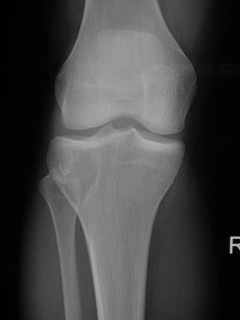

• Lytic lesion (Fig. 1, Fig. 2 & Fig. 3)

• Well-defined

• Geographic margins

• Eccentric

• Majority have well-defined sclerotic rims

• More aggressive lesions may have irregular margins

• Frequently produce endosteal erosion and cortical thinning

• Trabeculation may be seen

Fig. 1

Fig. 1-3: AP and Lateral plain x-rays of a benign fibrous histiocytoma shows an eccentric lytic lesion in the proximal tibia, well- demarcated with a prominent sclerotic rim. No soft tissue mass or trabeculations are seen.